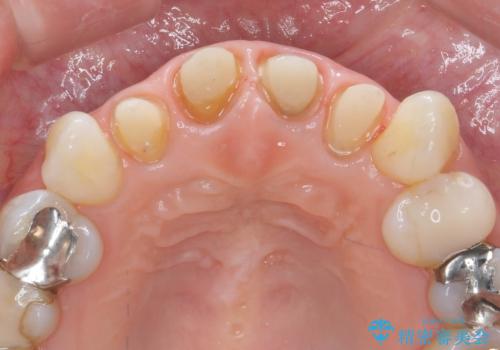

- 「黒ずんで、見栄えの悪い前歯をきれいにしたい。」と、前歯のセラミック治療を希望され来院されました。

全て根管治療のすでになされている歯の変色で、オールセラミッククラウンによる審美性の改善を計画します。